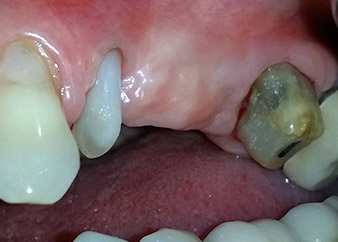

One month later, on the day of surgery, pain and inflammation at tooth 24 were minimal, but mobility of Miller class 2 was still present. After opening the flaps and cleaning the periapical and peri radicular infected tissue, the extent of the bone defect became obvious (Figs. 2 and 3).

At the buccal root, all vestibular and distal bone was missing. Attachment was essentially restricted to the palatal root, underlining the preliminary poor prognosis. Tooth 27 also showed a reduced horizontal attachment and a minimal apical rarefaction (cf. Fig. 1) without clinical symptoms.

However, we maintained our initial plan to retain both teeth as temporary bridge abutments during the six-months osseointegration period of the implants. At reentry, the situation would have to be reassessed. First, in an attempt to manage the endo-perio problem, the remaining root surface was carefully debrided with piezoelectric equipment (Piezomed, W&H, used with the spatula-shaped insert S1, originally designed for erosion of the lateral sinus wall) (Fig. 4).